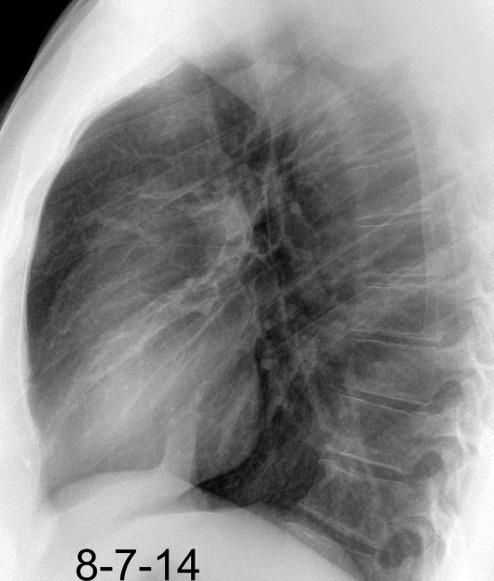

30 años

Borramiento de la banda PARA-aórtica por AdenoCa. de LII, no visible en 2005

Colapso de LII. TC: secreciones bronquiales.

Endoscopia tapón mucopurulento extraído